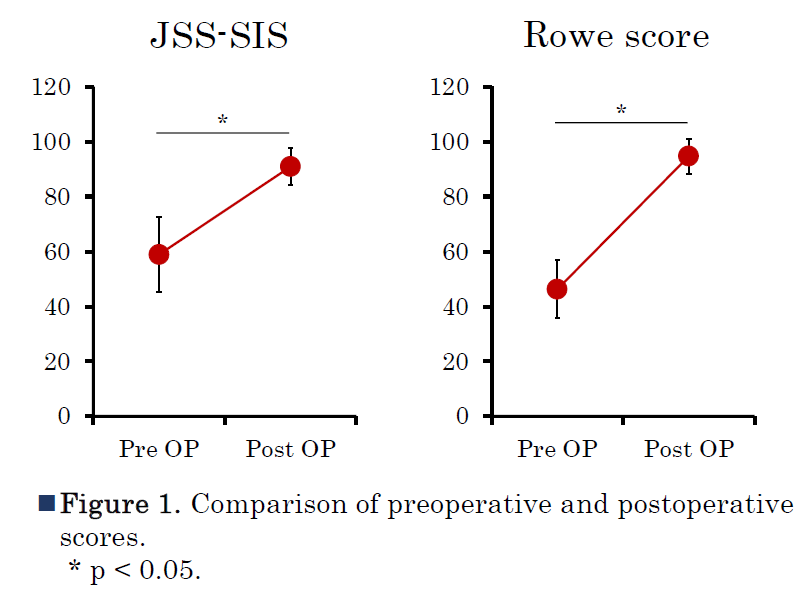

論文で証明された圧倒的な治療成績

当院における症例の臨床成績は、学術論文『肩関節』でも発表されています。

- 再脱臼率 3.2%: 一般的な術式では5〜20%とも言われる再脱臼率を、わずか3.2%にまで抑えています。

- スポーツ復帰率 82.1%: 受傷前と同等レベルでの競技復帰を実現。コンタクトスポーツ選手においても高い満足度を得ています。

- 早期リハビリテーション: 手術翌日から可動域訓練を開始。手術の固定力があるからこそ可能な、AR-Exならではのスピード感ある復帰プログラムです。